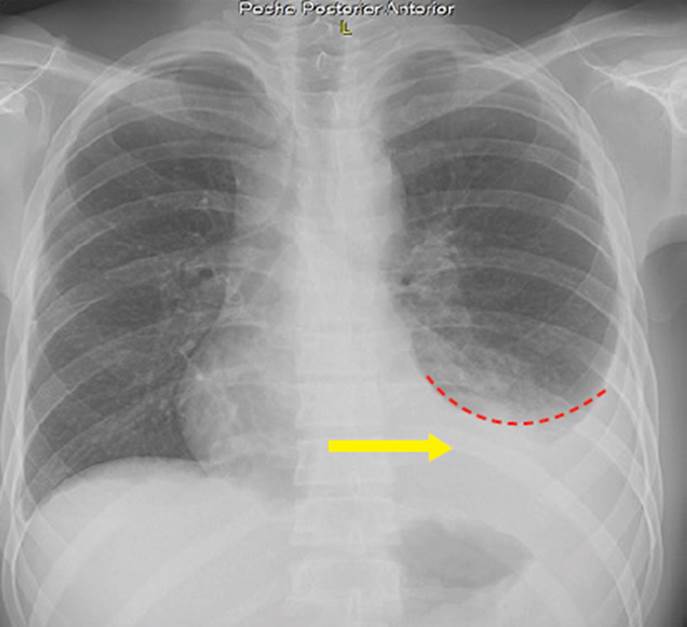

La tuberculosis multisistémica se define como una infección de TB que afecta el torrente sanguíneo, la médula ósea, el hígado o dos o más sitios o sistemas no contiguos, e incluye la TB miliar que afecta a los pulmones 4. Además, se presenta con mayor frecuencia en pacientes con coinfección por VIH y la presentación de la enfermedad puede estar relacionada con el nivel de inmunosupresión del paciente 5. En pacientes con VIH avanzado con recuento de células CD4 < 250 células/mm, la progresión de la enfermedad es marcadamente diferente en comparación con los pacientes con recuento de células CD4 más alto 6. El diagnóstico sigue siendo un desafío, ya que las manifestaciones clínicas son diversas, las pruebas microbiológicas dependen de procedimientos invasivos y el gold standard del cultivo de micobacterias o la histopatología de apoyo no está disponible en su mayoría 7. Reportamos una presentación inusual de TB multisistémica que afectó el sistema urinario, respiratorio y digestivo de un paciente varón de 19 años inmunodeprimido por VIH. Se describen y discuten el tratamiento y el factor etiológico más prevalente, el SIDA.

En la Tabla 1 se muestran los exámenes de laboratorio que se realizaron durante la hospitalización del paciente: baciloscopia en esputo con resultado negativo, baciloscopia en orina con resultado 5 BAAR y baciloscopia en heces que resultó positiva (+), ecografía torácica con reporte de líquido libre en ambos hemitórax, un volumen de 400 ml en el hemitórax izquierdo y 150 ml en el derecho; radiografía de tórax que muestra derrame pleural bilateral con predominio izquierdo (Figura 1); ecografía abdominal con hallazgos de esplenomegalia y nódulos hipoecogénicos (Figura 2); test de adenosina deaminasa en líquido pleural con valor 33. Los resultados de carga viral para VIH fueron 181 000 copias/ml y CD4: 63.

El síndrome de inmunodeficiencia adquirida, SIDA, es la fase más grave de la infección por el VIH (fase 3). Una persona recibe el diagnóstico de SIDA cuando los recuentos de células CD4+ son menores a 200 células/mm3, o cuando comienza a presentar ciertas infecciones oportunistas 10. Estas infecciones se manifiestan según la gravedad de la supresión de los recuentos de CD4+, por lo que diversos estudios 11,12 clasifican su aparición en función de estos niveles. En todo paciente con SIDA, se busca alguna enfermedad concomitante que pueda exacerbarse por la inmunodeficiencia; además, se evalúa su estado mental para poder tener un buen control psiquiátrico y realizar un adecuado tratamiento antirretroviral que asegure la adherencia del paciente.

En nuestro caso, el paciente fue sometido a una prueba sérica 5 días después del internamiento, y 3 días después recibió los resultados con un recuento de CD4+ con valor de 63; por lo que ingresa al rango de infecciones oportunistas que aparecen con valores de CD4+ entre 500 a 100 cel/mm3. Como se menciona en la Tabla 2, puede aparecer cualquier tipo de infección oportunista de ese rango, pero con mayor prevalencia a la aparición de criptosporidiosis, criptococosis, microsporidiosis e infección por virus del herpes simple (VHS), los cuales aparecen desde un recuento < 100 cel/mm3 11,12.